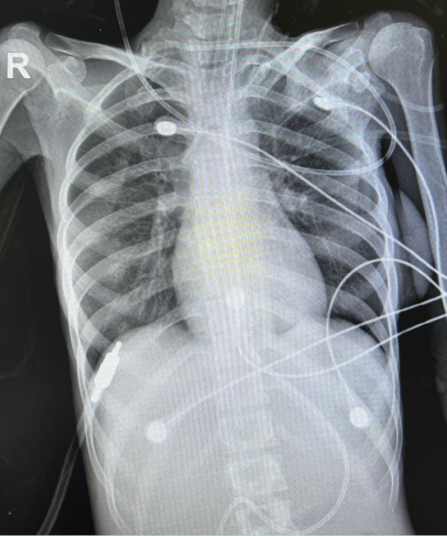

8月2日床旁胸片显示右肺多发类结节样改变,两下肺炎症较前增多,两侧少量胸腔积液(图3)。血常规及生化等检查示:WBC 8.0×109/L,NEU% 91.6%,Hb 56 g/L,PLT 33×109/L,CRP 45.69 mg/L,ALB 31.5 g/L,BUN 36.5 mmol/L,Cr 62.3 μmol/L,PT 14.7 s,APTT 34.0 s,D-二聚体2.00 μg/ml。

图3  患者胸部X线片(2022年8月2日)